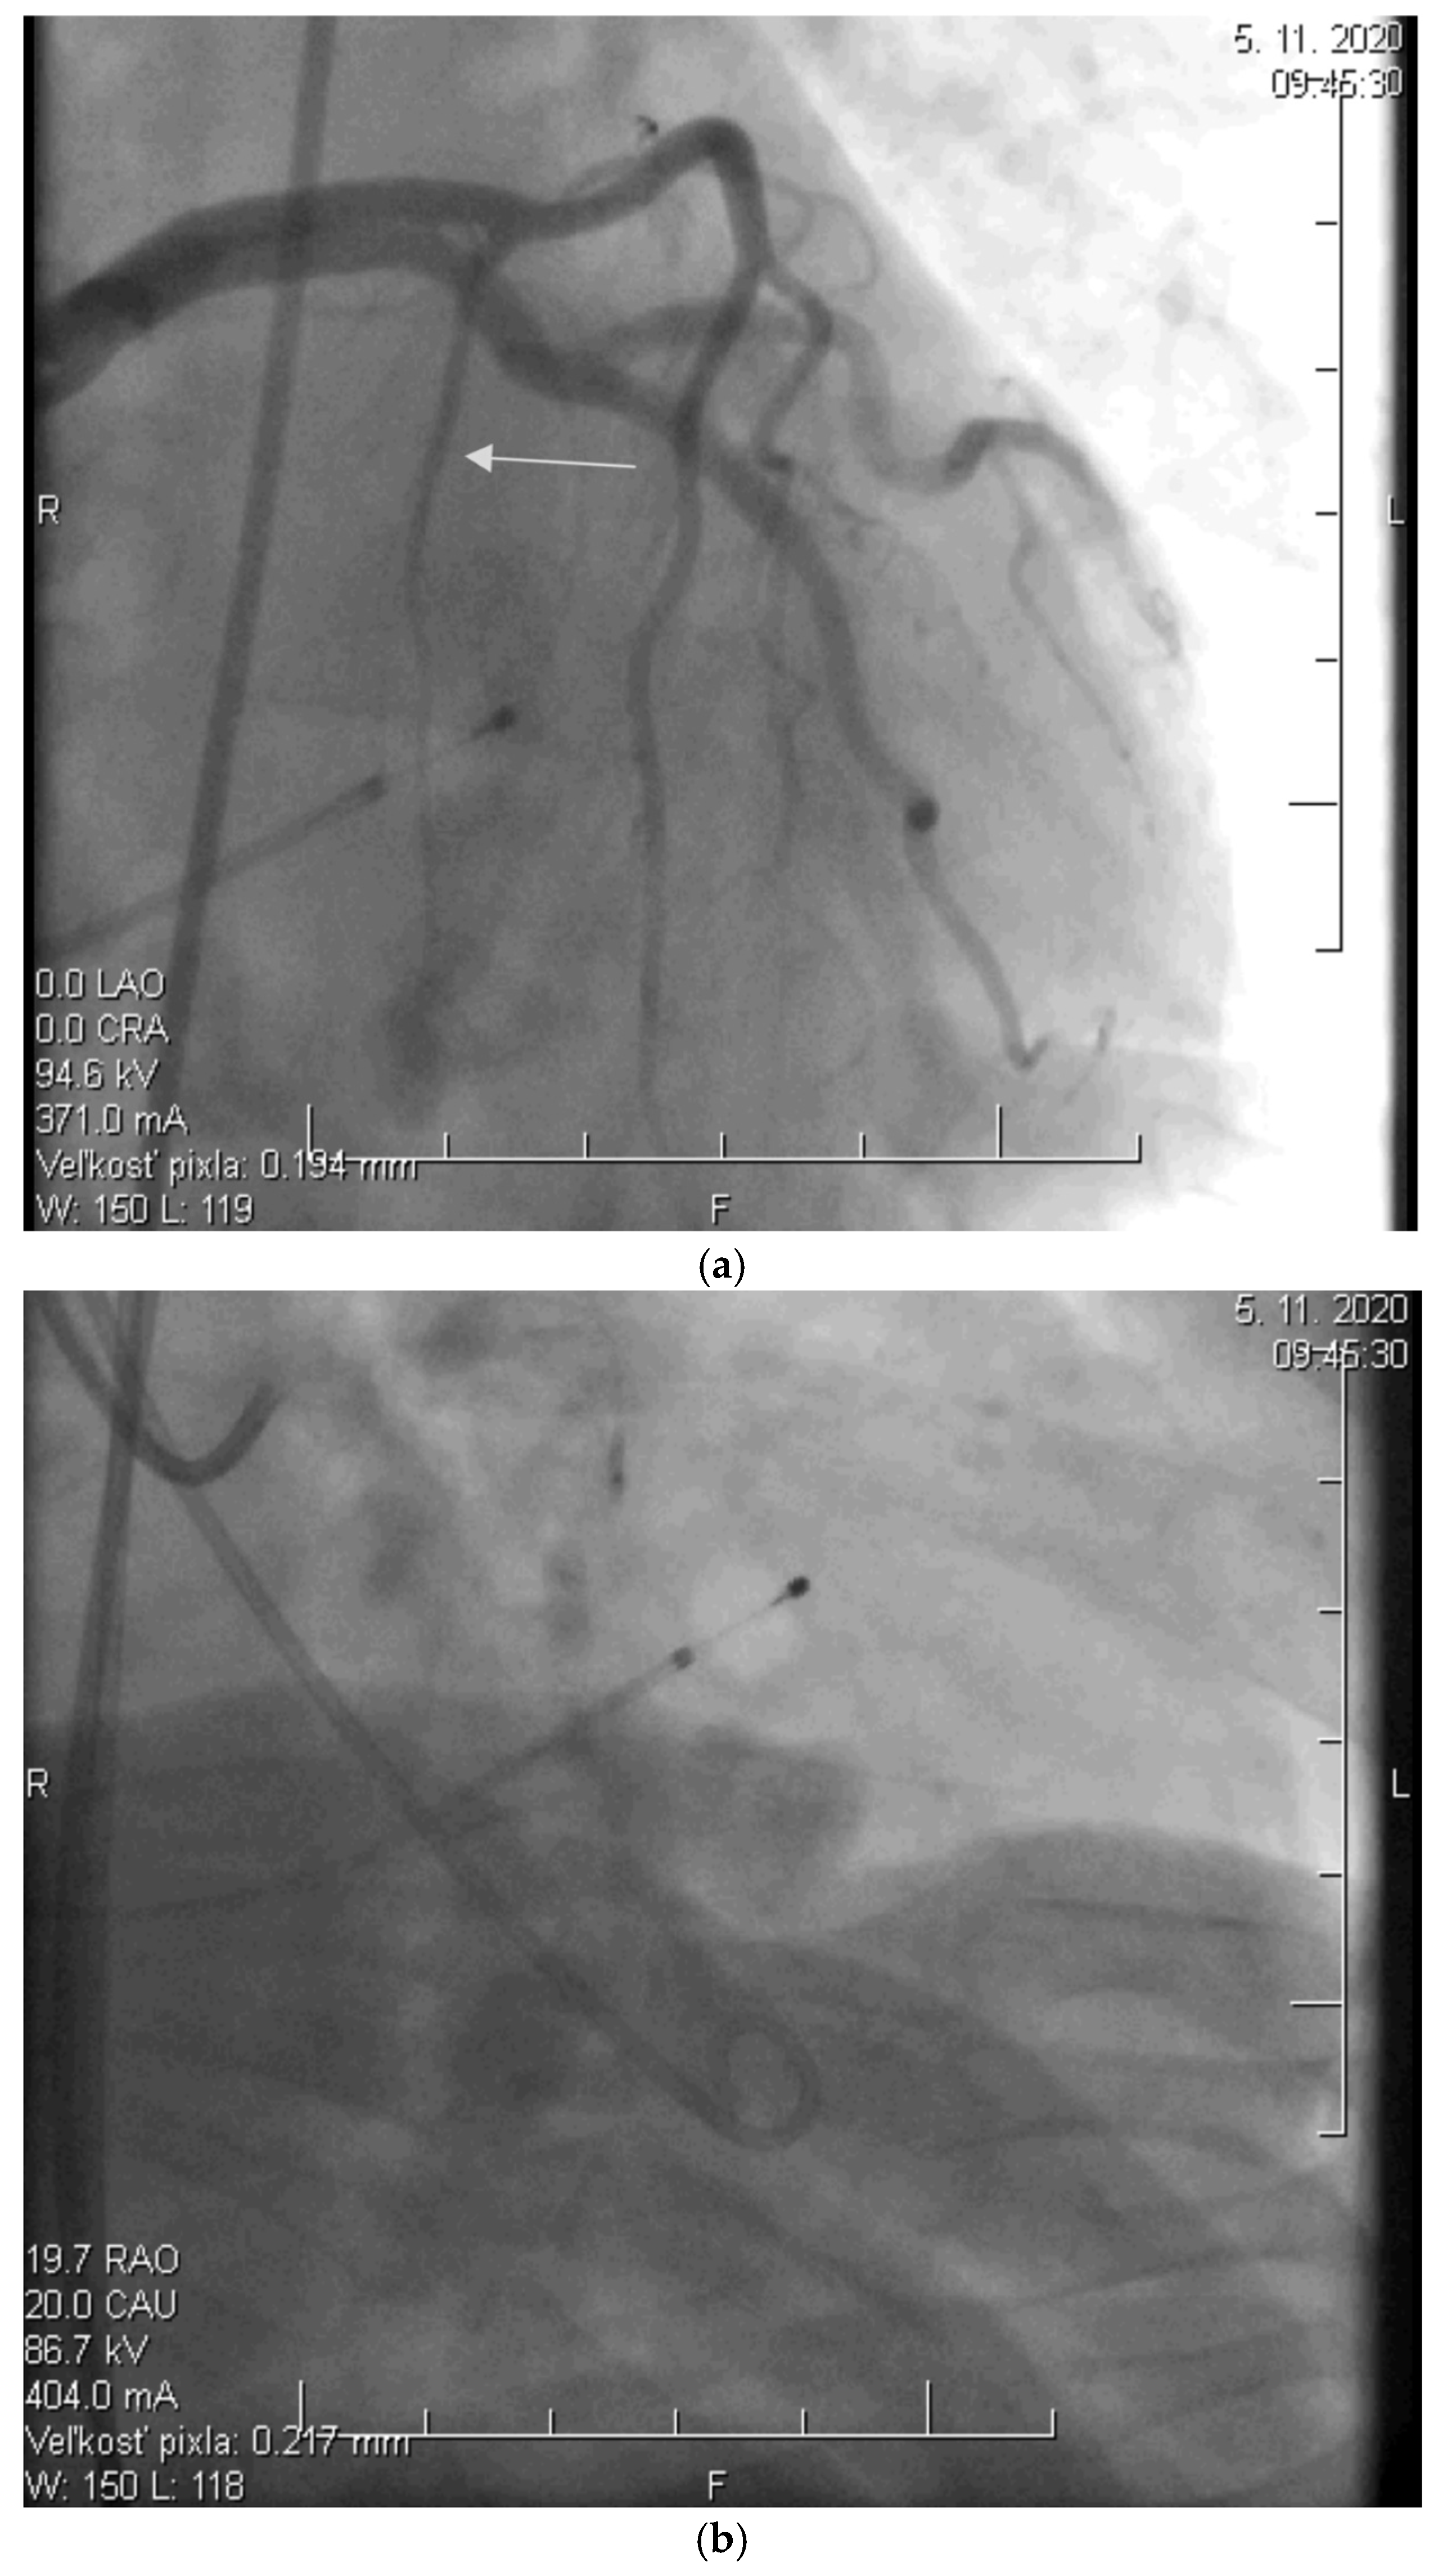

2.2. Alcohol Septal Ablation